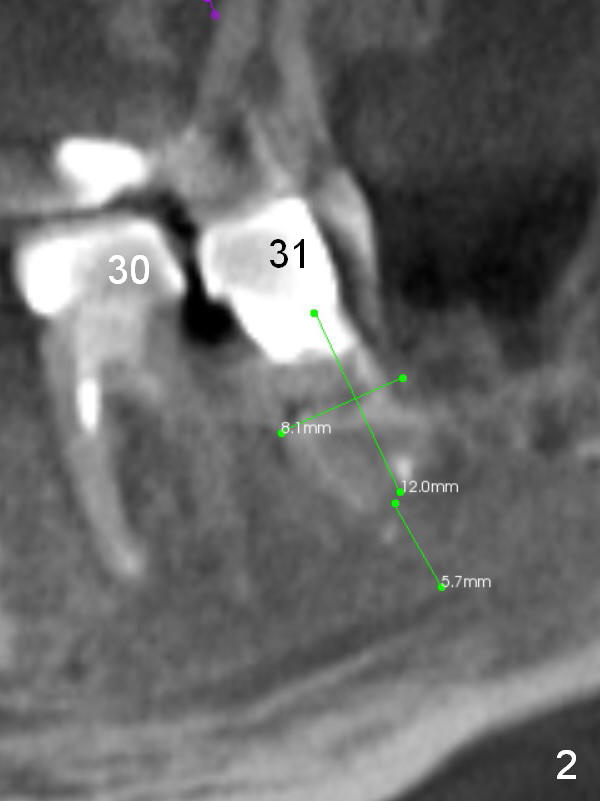

A 39-year-old man (ZC) fractures the lingual portion of the tooth #31 while eating peanut during Christmas (Fig.1 green arrows), a few months finishing #28,29 implant crowns. It fractures between the large amalgam (Fig.3 A) and the lingual portion of the tooth (L). It should be subgingival and nonsalvageable. Prepare crown prep or immediate implant. If the latter is indicated, the socket will be treated with 2% Xylocaine/1:50,000 Epinephrine. The distance between the apex of the socket and the Inferior Alveolar Canal is >5 mm (Fig.2,4). If osteotomy is controlled 3 mm beyond the apex of the socket, it is safe (Fig.3,5). A 5.9x10 or 12 mm implant should be able to engage to the buccal and lingual walls for additional stability (Fig.5), while there will be mesial and distal gaps to be filled with bone graft (Fig.3 red dots).